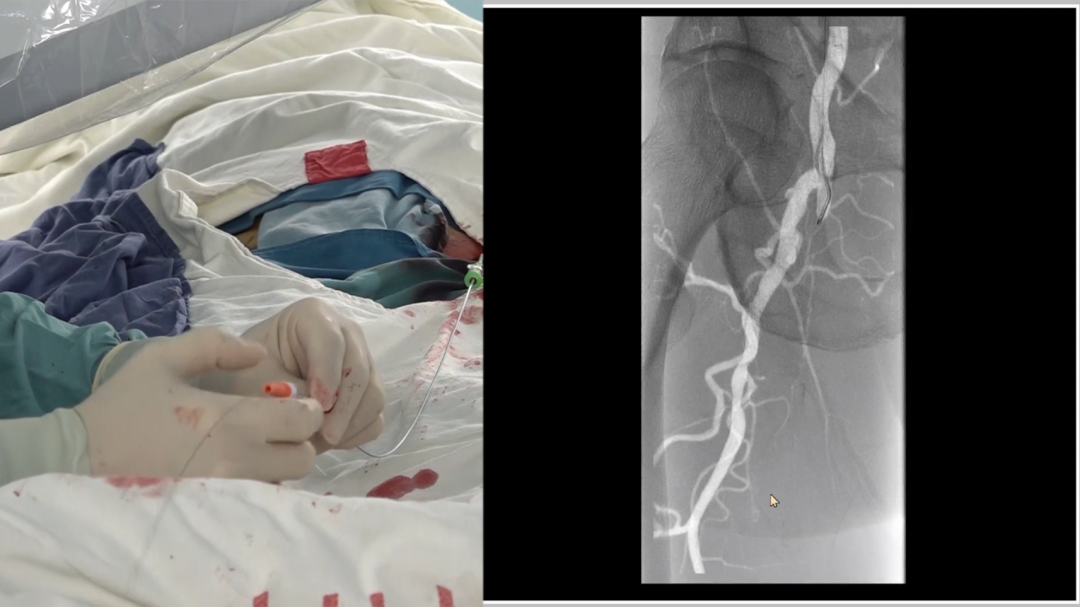

造影确认病变:长段闭塞,流出道尚可

造影显示右侧股动脉自起始段起长段闭塞,远端腘动脉及膝下动脉经股深侧枝显影,流出道条件尚可,为手术提供了基础。